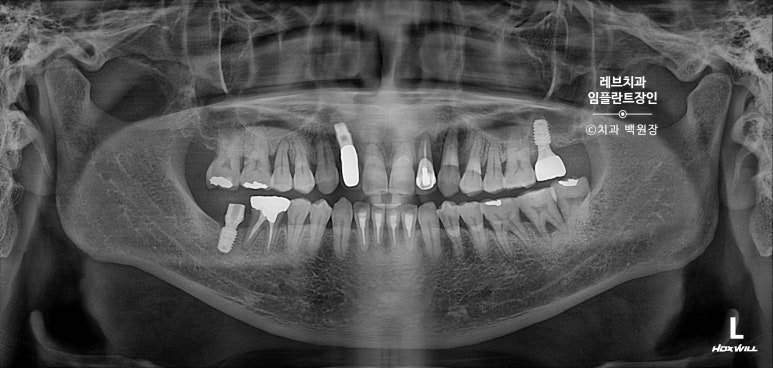

치과용 파노라마 사진을 보시면, 아주 짧은 뿌리만이 남아있는 것을 보실 수 있어요..

고개를 돌려서 보면, 뿌리만 있는 치아들이 몇개 보이고...

치아 목부위 (치경부)에 충치가 있는 치아들도 여러개 보여요.

치과용 파노라마 사진에서도 왼쪽 위 송곳니 주변으로 잇몸뼈가 사라진 것을 보실 수 있는데요,

확대해볼 수 있는 치근단 방사선 사진을 보시면, 송곳니 뿌리 주변으로 거무딩딩하게 뼈가 없어진 것을 보실 수 있습니다.

만성치주염으로 상당히 많은 양의 잇몸뼈가 파괴되었죠.